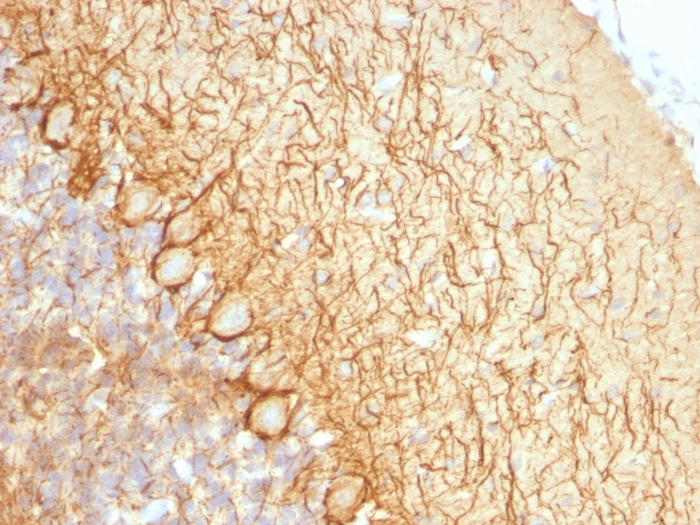

IHC-P analysis of human cerebellum tissue using GTX34902 NF-L antibody [NR-4].